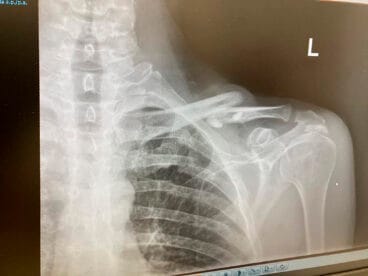

28 de enero de 2024 - 09:36 1 de 5Foto SiguienteVer el artículo original: Cuando un mal golpe con los jabalíes te manda al hospital: ¿es posible combatir la plaga en la Marina Alta? Ramón Mut tras recibir el alta del hospital Radiografía de la clavícula rota del ciclista Ramón Mut, ciclista de Ondara en el hospital después del accidente con los jabalíes Ramón Mut, ciclista de Ondara en el hospital después del accidente con un jabalí Jabalíes dentro de Xàbia